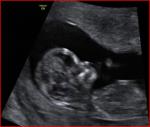

So just had ultrasound and I am measuring 6wks 1day. Heart beat was 122 and I ovulated on the right sideThat's not a good sign, right? Low heartbeat= boy, right ovary=boy....

That's not a good sign, right? Low heartbeat= boy, right ovary=boy....